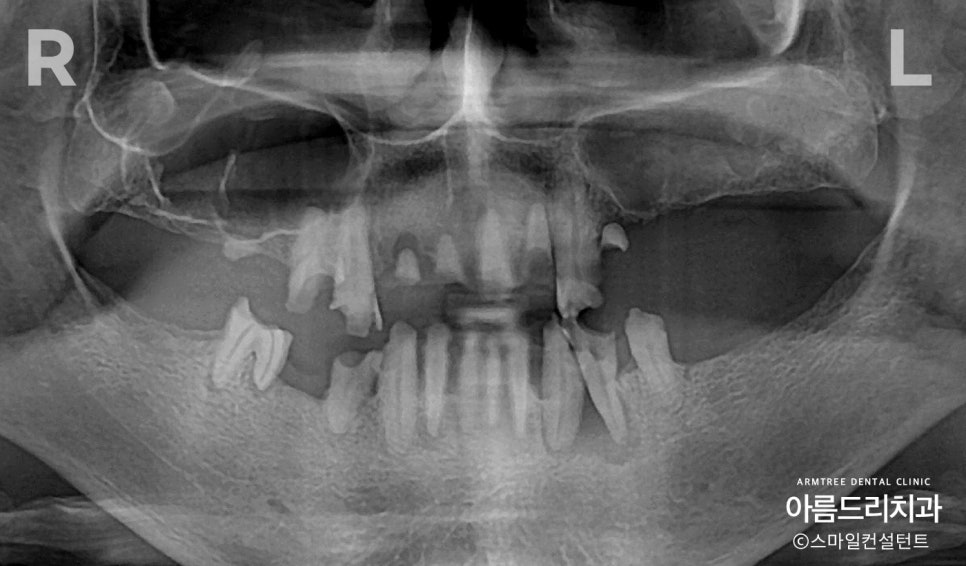

전체임플란트 전악임플란트 전후 아름드리치과 진료일기 오늘은 전체 임플란트 케이스를 보여드리겠습니다. 젋은 여자분이신데, 치아가 일찍 상실되었습니다. 치아가 상실된 채로 오랜 기간 지내게 되면 치아를 지탱해주고 있던 치조골이 점점 없어지면서 얼굴모양도 많이 변하게 됩니다. 이렇게 치조골이 녹아 없어지면서 얼굴모양...

오늘은 전체 임플란트 케이스를 보여드리겠습니다.

젋은 여자분이신데, 치아가 일찍 상실되었습니다.

치아가 상실된 채로 오랜 기간 지내게 되면

치아를 지탱해주고 있던 치조골이 점점

없어지면서 얼굴모양도 많이 변하게 됩니다.

그런데 이미 치조골이 많이 없어서 전체임플란트

치료를 계획하는데 어려움이 많았습니다.

전악임플란트 치료전 사진(상악/하악)

환자분의 전체임플란트 치료 전 사진

(상악/하악)부터 보여드리도록 하겠습니다.